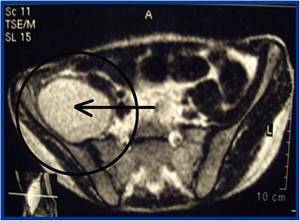

Максимальная информативность МРТ связана с возможностью визуализации отека костного мозга, параоссальных мягких тканей, а также гнойных затеков

Это особенно важно в диагностике внутритазовых гнойников, когда клинических, да ультразвуковых методов бывает недостаточно

Рис. 3. МРТ таза. Поперечный срез. В подвздошной ямке определяется скопление гноя. Исследование позволило